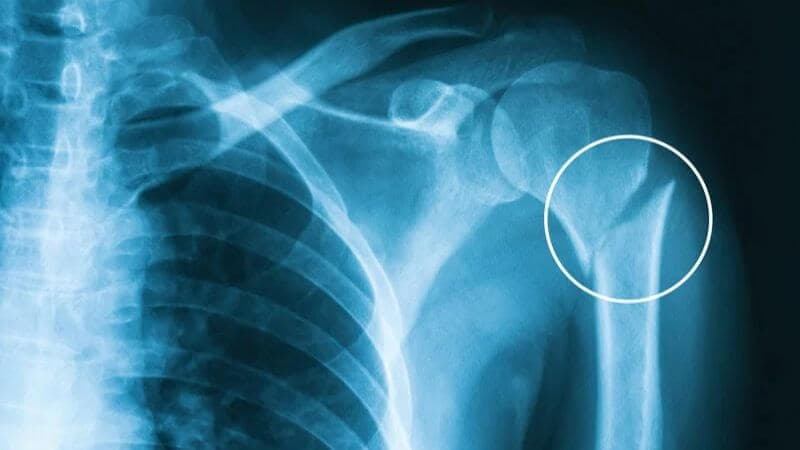

Gãy xương cánh tay chiếm khoảng 3% trong các trường hợp gãy xương cánh tay nói chung. Nguyên nhân gây gãy xương cánh tay là do chấn thương trực tiếp khi vật cứng đập vào làm gãy xương hoặc khi ngã chống tay xuống đất.

Phẫu thuật gãy xương cánh tay là phương pháp điều trị ngoại khoa giúp cố định phần xương cánh tay bị gãy, phục hồi phần xương gãy và lấy lại chức năng vận động bình thường.

Gãy xương cánh tay có thể gặp biến chứng sớm là liệt dây thần kinh quay, thương tổn động mạch cánh tay, chèn cơ vào giữa 2 đầu xương gãy cản trở nắn chỉnh ổ gãy hoặc biến chứng muộn do can xương xù to, sẹo phần mềm xơ cứng đè ép vào dây thần kinh quay, chậm liền xương, khớp giả, liền xương xấu, gập góc, chồng, xoay, lệch sang bên, hạn chế vận động khuỷu và vai…